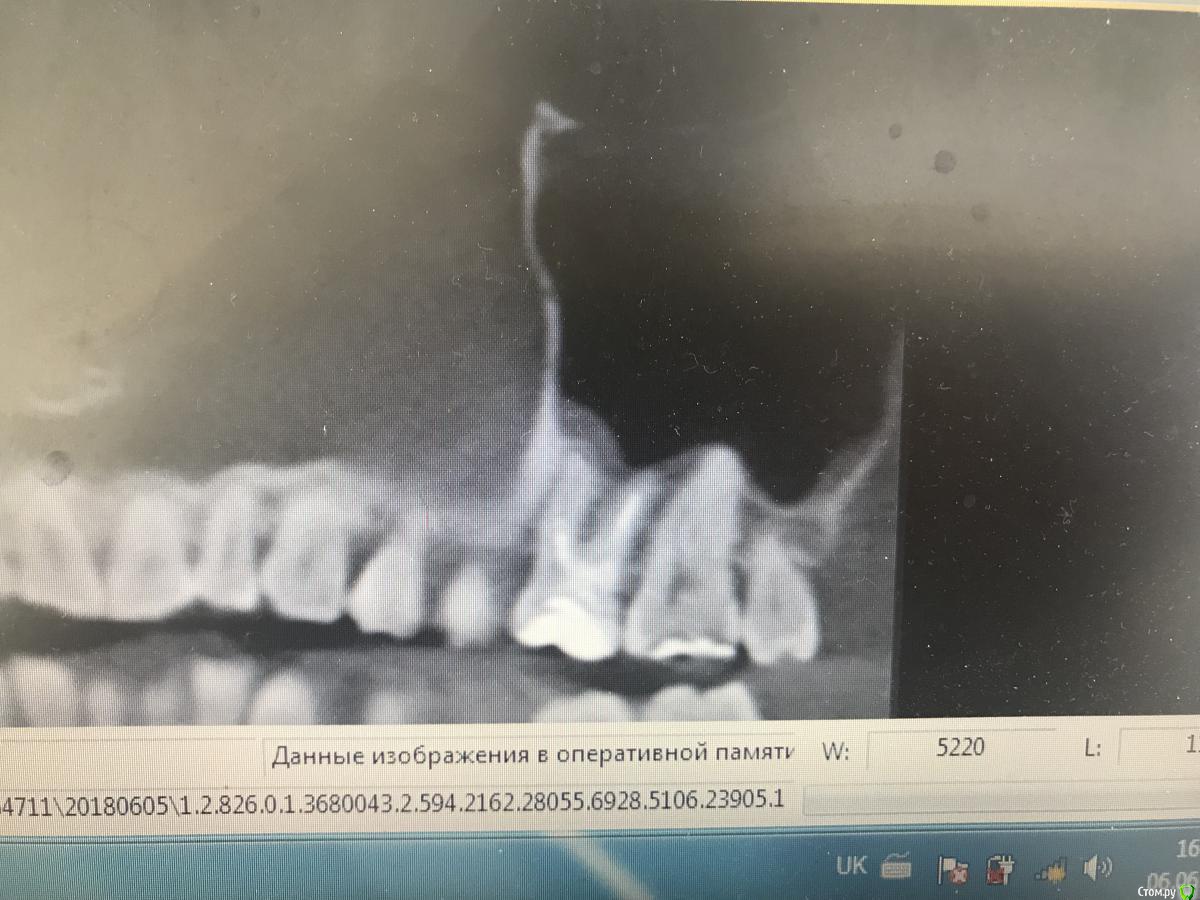

dr.Dre Опубликовано 6 июня, 2018 Поделиться Опубликовано 6 июня, 2018 (изменено) Добрый день ,коллеги такой клинический случай ,пациента нос заложен постоянно лор напривил сказал гайморит от зубов ,я думаю , что причина в 26 ,что скажите? Изменено 6 июня, 2018 пользователем dr.Dre Ссылка на комментарий

Дмитрий Л. Опубликовано 6 июня, 2018 Поделиться Опубликовано 6 июня, 2018 извините пожалуйста загрузил с телефона, у меня есть кт как можно загрузить на форум?Загрузить на файлообменник или облако (гугл диск, к примеру) и затем ссылку сюда. Я бы обратил внимание на 16. Но данных мало вы предоставили... гайморит... какой, 1-, 2-сторонний? Срезы непонятные Заложенность носа это ещё не гайморит. Жалобы на "зубы"? Перкуссия и т.д. Ссылка на комментарий

johniola Опубликовано 7 июня, 2018 Поделиться Опубликовано 7 июня, 2018 Где там гайморит? Геморрой может и есть,а вот гайморита не вижу Ссылка на комментарий